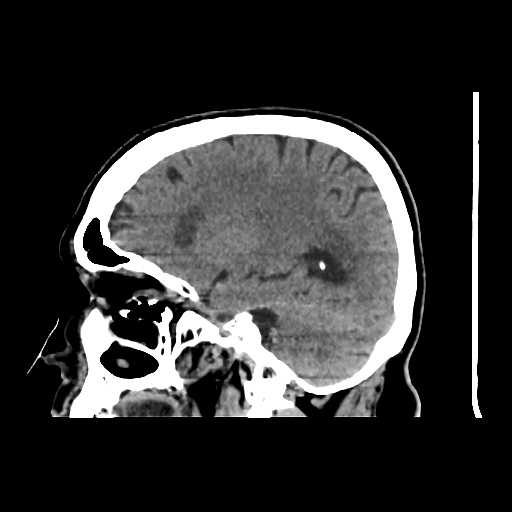

A 75 years old woman with DM-2 since 3 years

Patient O/E images:

C/O: Breathlessness X 2-3 day's

Vomiting 1-2 episode since last night

Cough X 2-3 day's

H/O: unconsiouness since few hour's at home around 10:30 pm

K/C: DM / HTN since 2-3 year's